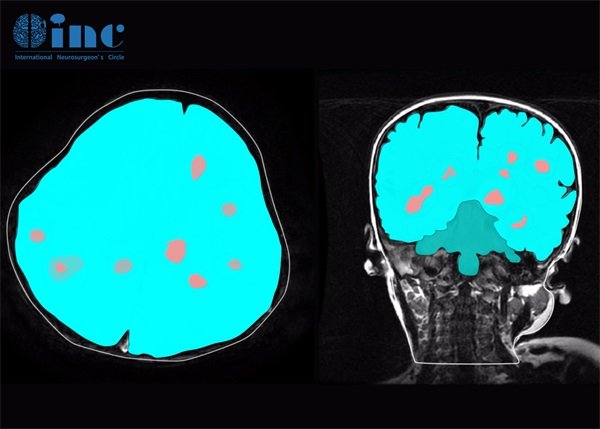

2. 影像学检查结果

影像学检查如CT和MRI是确认脑海绵状血管瘤的重要手段。报告中常见的术语包括“高信号”或“低信号”,这些信号的存在与血管瘤的位置、大小及性质密切相关。通常,高信号代表该区域有丰富的血液供应,可能意味着血管瘤的活跃状态。